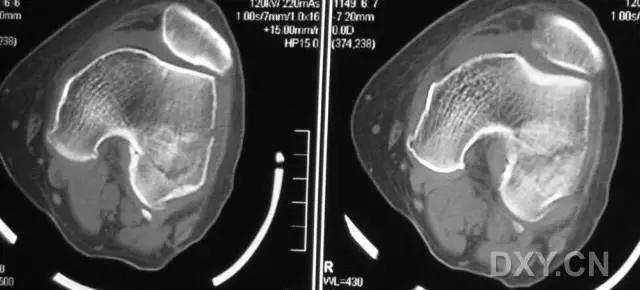

5. Hoffa 骨折

指股骨远端冠状面的骨折。

病例 1:一般股骨髁间、髁上粉碎骨折中含 Hoffa 骨折的不少见,但单纯后髁骨折则很少见。

水平位 CT

第 2 例

第 3 例